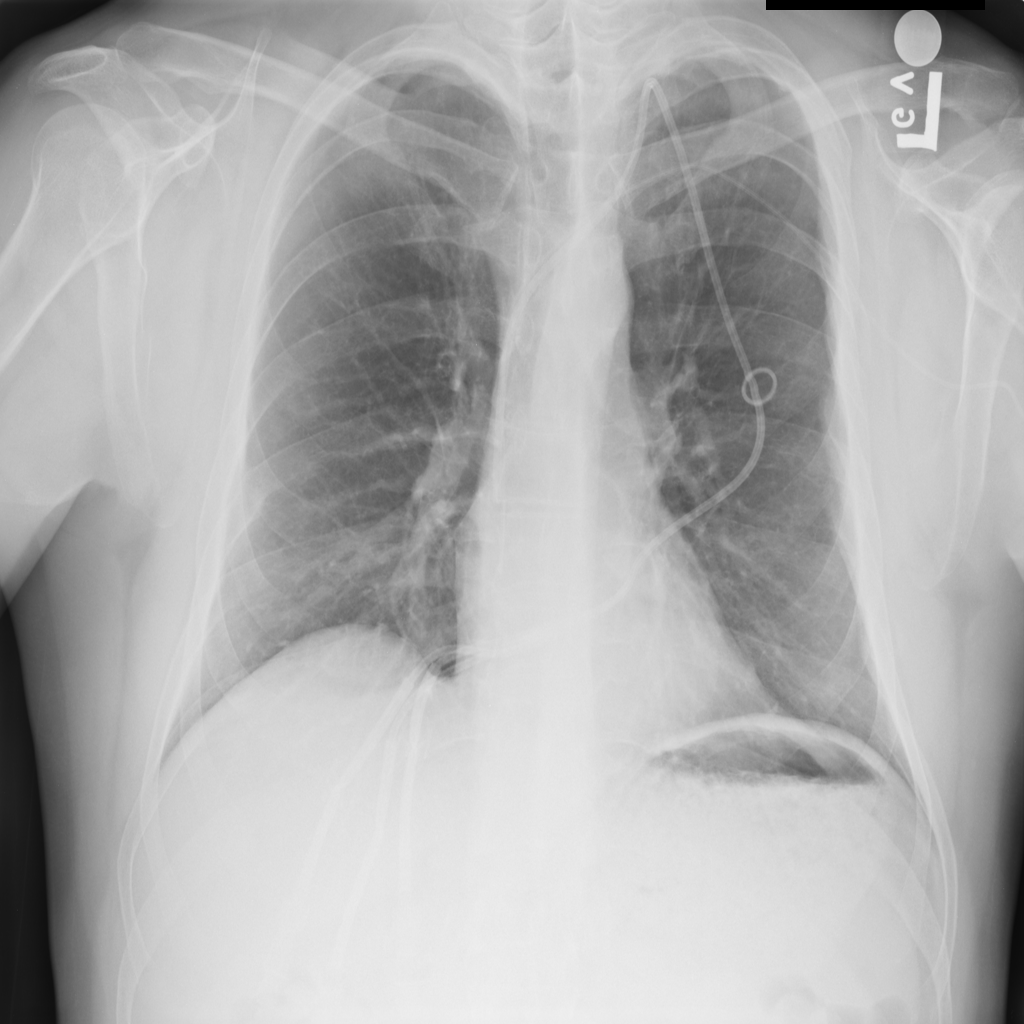

Showing up to 90 reference images for Pneumonia.

PAT-C0E5 · IMG-015Pneumonia

PAT-C0E5 · IMG-015

AP